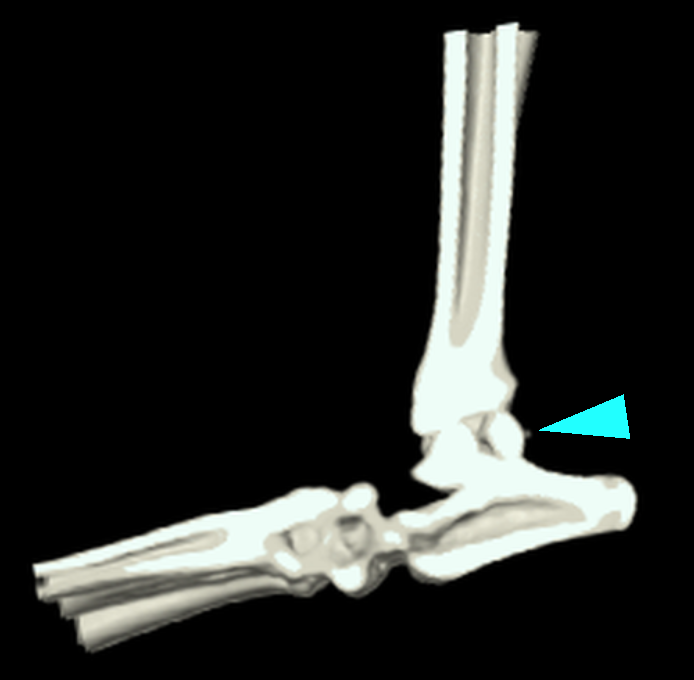

CT画像検査による3D画像検査になります。矢印の部分が遊離してしまっている骨片となります。